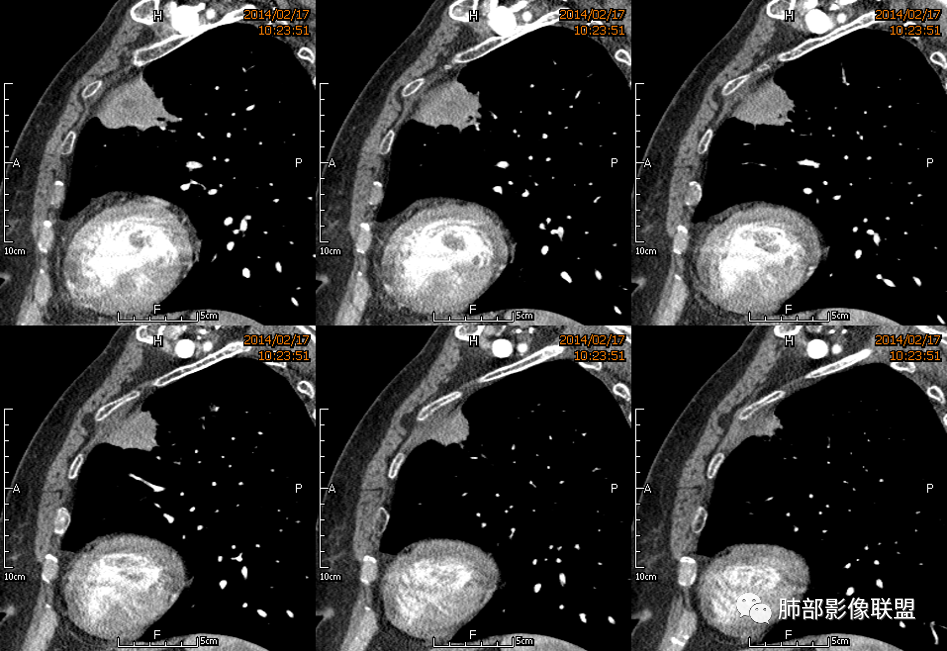

1、坏死区环形强化,指向慢性脓肿。

2、坏死区有血管,基本排除结核。

3、这个卫星灶,更进一步定了大方向,炎性。

※综上所述,看到这四幅图,基本能够准确诊断炎性※

3.病灶密度不均,中央坏死液化并见气泡影,支气管及血管贴边进入,较均匀环形强化(显示多层结构),未见明确壁结节。

3.病灶易坏死液化,环形强化,支气管及血管贴边进入,“火焰”样边缘轮廓,更符合炎性块影的特点。